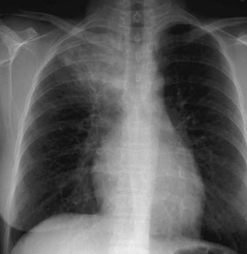

Chest pain

Navin M. Amin, MD